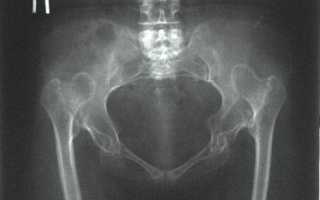

Дисплазия — это врожденный дефект строения ТБС, для которого характерна неправильная ориентация суставных компонентов. Дисконгруэнтность головки бедренной кости и вертлужной впадины приводит к функциональной перегрузке определенных частей сустава. Постоянная механическая травматизация вызывает дегенеративные изменения в суставных хрящах, капсуле и субхондральных костных структурах. В результате у больного развивается ранний деформирующий остеоартроз.

Тяжелая степень дисплазии.

По разным литературным данным, врожденные дефекты строения ТБС приводят к развитию диспластического коксартроза в 40-87% случаев.